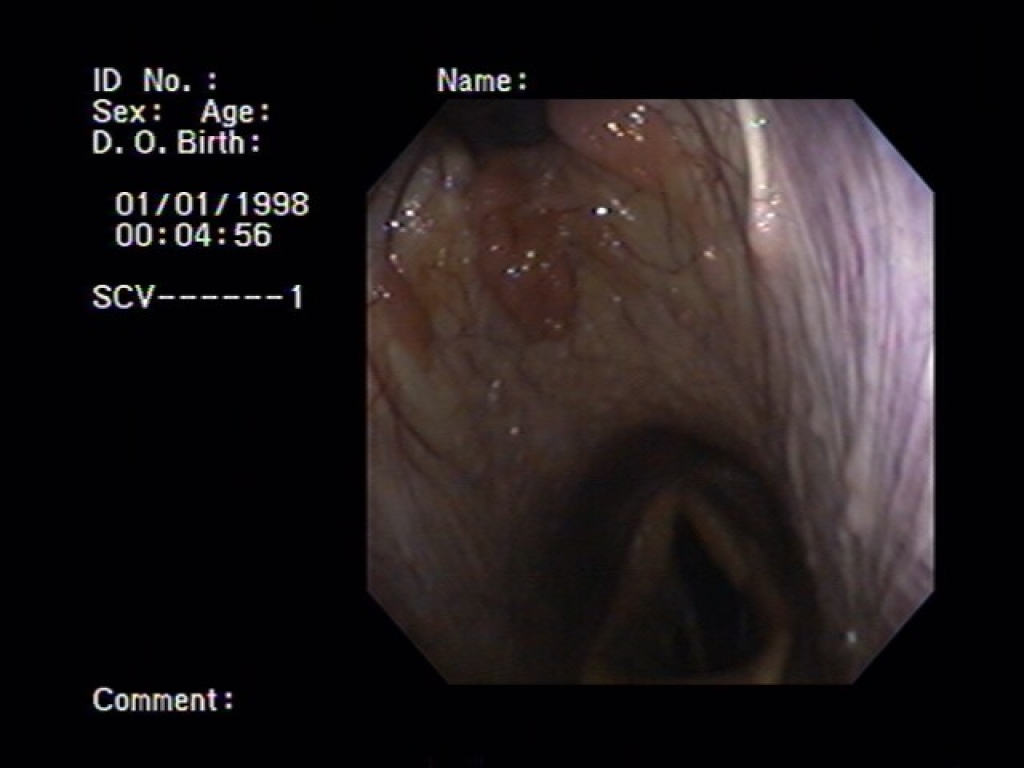

Bij een bronchoscopie wordt er via de neus een dunne slang met een camera naar binnen gebracht. Via deze camera kunnen we de luchtwegen bekijken.  We beginnen meestal in de keel. We kijken dan naar de uitmondingen van de luchtzakken, het strottenhoofd, de stembanden en het slijmvlies van de keel. Indien nodig kunnen we ook in luchtzakken kijken met de bronchoscoop. Vervolgens kunnen we met de bronchoscoop tussen de stembanden door de luchtpijp in. In de luchtpijp kijken we hoeveel slijm daar aanwezig is en of er nog andere tekenen zijn van een ontsteking. Meestal kijken we al laatste naar de neusgangen en neusholte. Op het moment dat we slijm of andere afwijkingen vinden kunnen we hier via de bronchoscoop ook gelijk een uitstrijkje van maken voor bacterieel onderzoek.

Linksbovenin is de keelholte in beeld gebracht. Rechtsboven is het strotteklepje met de stembanden daarachter van dichtbij in beeld gebracht. Het linker plaatje is van de luchtpijp.